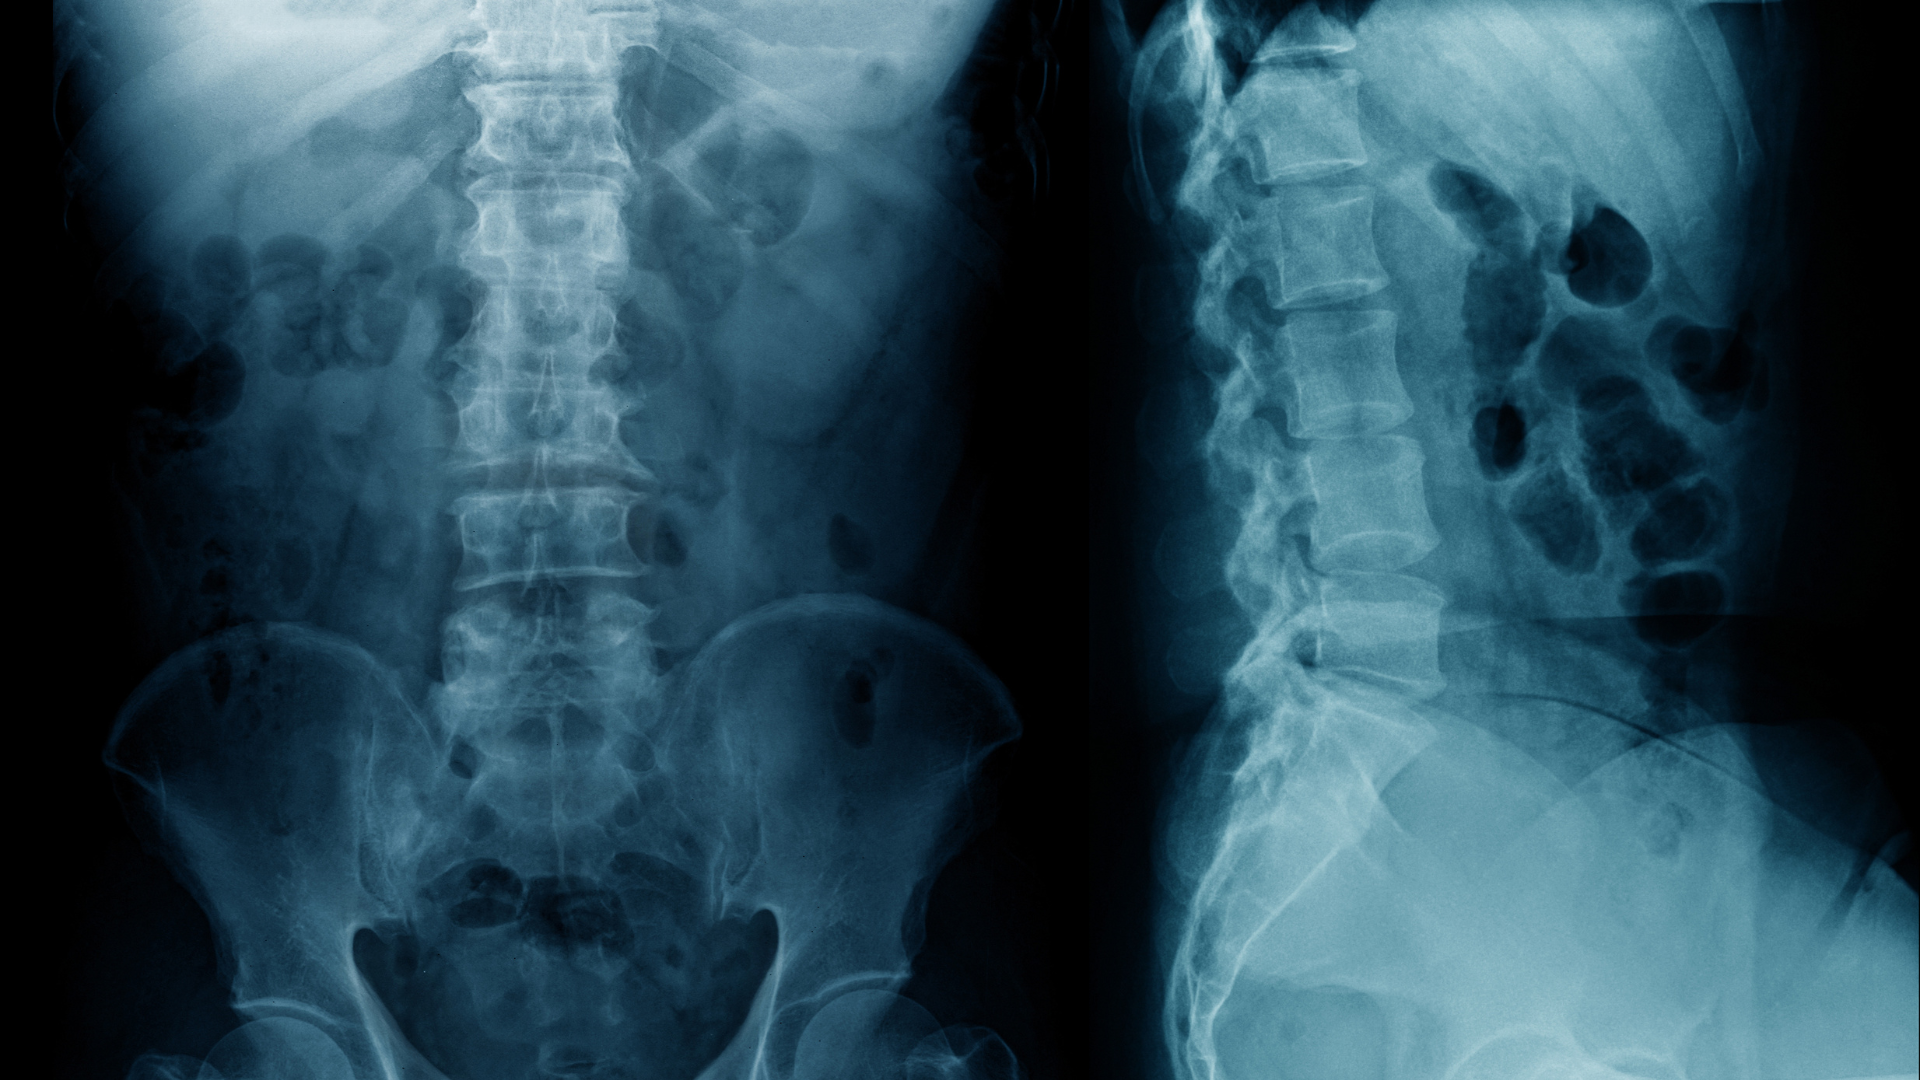

Để xác định nguyên nhân và mức độ tổn thương, bác sĩ có thể chỉ định các phương tiện chẩn đoán hình ảnh, bao gồm:

- X-quang để đánh giá tổn thương xương và khe khớp.

- Siêu âm khớp giúp phát hiện tràn dịch và viêm mô mềm.

- MRI để đánh giá chi tiết sụn, dây chằng và mô mềm quanh khớp.

- CT scan trong một số trường hợp cần hình ảnh chi tiết hơn.